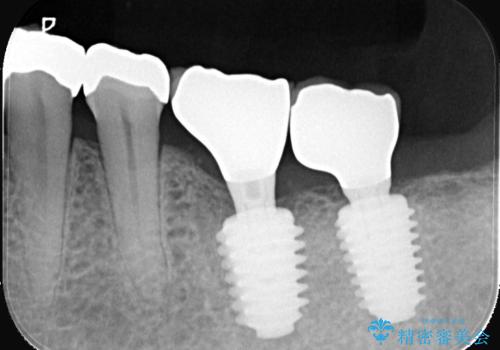

- 治療計画

今回の治療では、まず左下6番と7番の欠損部に、骨の状態を考慮しながら慎重に2本のインプラントを埋入しました。インプラント体と骨がしっかりと結合するのを待った後、最短の期間で最終的な被せ物を装着するための精密な型取りを実施。最終的に、周囲の歯と調和した審美性の高いセラミック製の歯を装着しました。